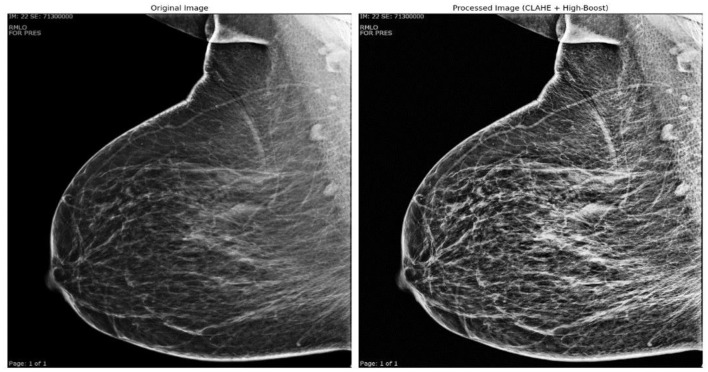

数字化乳房x线摄影对良性和恶性模式的分类是诊断乳腺癌的关键步骤,有助于早期发现并可能挽救许多生命。不同的乳房组织结构往往模糊和隐藏乳房问题。在数字乳房x光检查中对令人担忧的区域(良性和恶性模式)进行分类是放射科医生面临的重大挑战。即使对专家来说,最初的视觉指标也是微妙和不规则的,使识别变得复杂。因此,放射科医生需要一种先进的分类器来帮助识别乳腺癌和对关注区域进行分类。本研究提出了一种使用乳房x线摄影图像进行乳腺癌分类的增强技术。该收集包括来自约旦科技大学阿卜杜拉国王大学医院(KAUH)的真实数据,包括来自5000名18-75岁患者的7205张照片。将图像分类为良性或恶性后,通过重新缩放、归一化和增强进行预处理。采用高升压滤波和对比度限制自适应直方图均衡化(CLAHE)等多融合方法提高图像质量。我们创建了一个独特的残差深度网络(RDN)来提高乳腺癌检测的精度。将建议的RDN模型与MobileNetV2、VGG16、VGG19、ResNet50、InceptionV3、Xception和DenseNet121等著名模型进行了比较。RDN模型的准确率为97.82%,准确率为96.55%,召回率为99.19%,特异性为96.45%,F1评分为97.85%,验证准确率为96.20%。研究结果表明,所提出的RDN模型是一种利用乳房x线摄影图像进行早期诊断的优秀工具,当与多融合和有效的预处理方法相结合时,可以显著提高乳腺癌的检出率。

The categorization of benign and malignant patterns in digital mammography is a critical step in the diagnosis of breast cancer, facilitating early detection and potentially saving many lives. Diverse breast tissue architectures often obscure and conceal breast issues. Classifying worrying regions (benign and malignant patterns) in digital mammograms is a significant challenge for radiologists. Even for specialists, the first visual indicators are nuanced and irregular, complicating identification. Therefore, radiologists want an advanced classifier to assist in identifying breast cancer and categorizing regions of concern. This study presents an enhanced technique for the classification of breast cancer using mammography images. The collection comprises real-world data from King Abdullah University Hospital (KAUH) at Jordan University of Science and Technology, consisting of 7,205 photographs from 5,000 patients aged 18-75. After being classified as benign or malignant, the pictures underwent preprocessing by rescaling, normalization, and augmentation. Multi-fusion approaches, such as high-boost filtering and contrast-limited adaptive histogram equalization (CLAHE), were used to improve picture quality. We created a unique Residual Depth-wise Network (RDN) to enhance the precision of breast cancer detection. The suggested RDN model was compared with many prominent models, including MobileNetV2, VGG16, VGG19, ResNet50, InceptionV3, Xception, and DenseNet121. The RDN model exhibited superior performance, achieving an accuracy of 97.82%, precision of 96.55%, recall of 99.19%, specificity of 96.45%, F1 score of 97.85%, and validation accuracy of 96.20%. The findings indicate that the proposed RDN model is an excellent instrument for early diagnosis using mammography images and significantly improves breast cancer detection when integrated with multi-fusion and efficient preprocessing approaches.